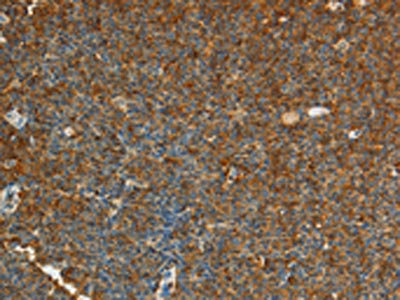

The image on the left is immunohistochemistry of paraffin-embedded Human lymphoma tissue using CSB-PA116506(ADM Antibody) at dilution 1/20, on the right is treated with synthetic peptide. (Original magnification: ×200)